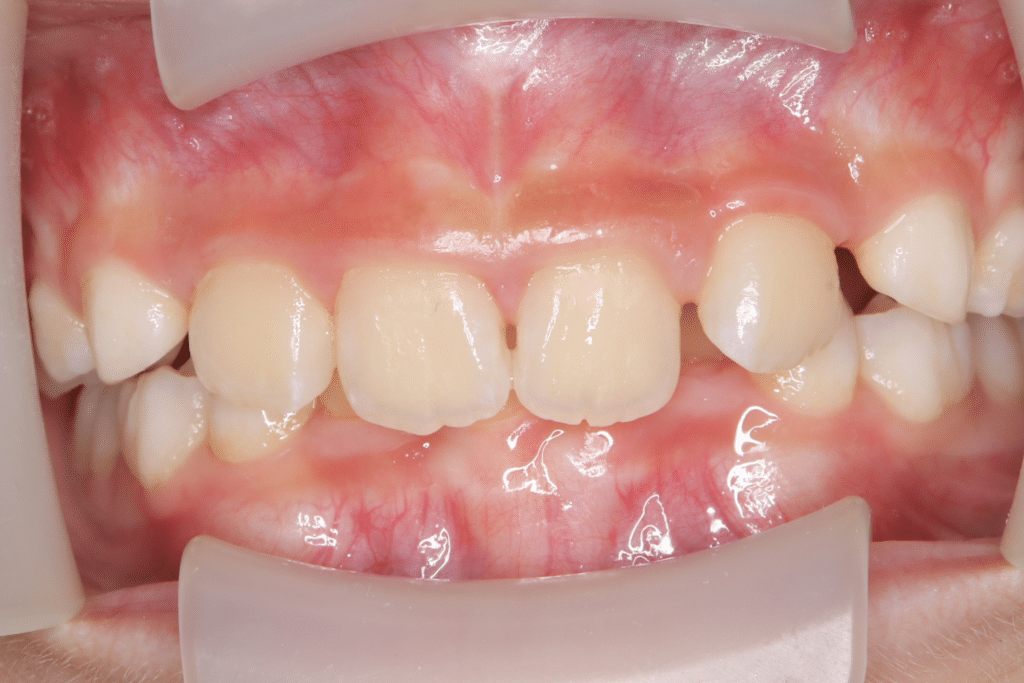

過蓋咬合

(9歳3ヶ月)

開始後1ヶ月